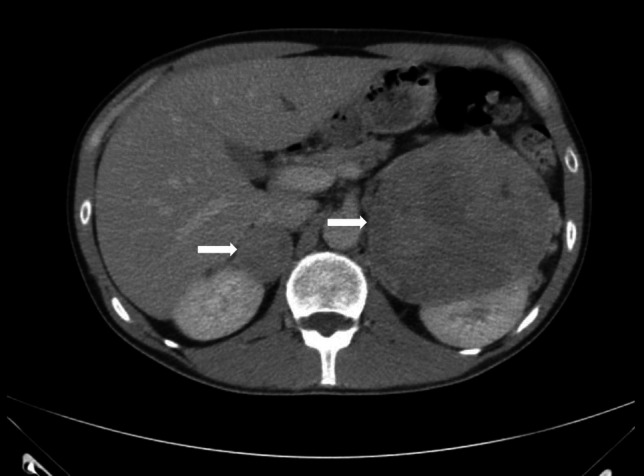

Abstract Image